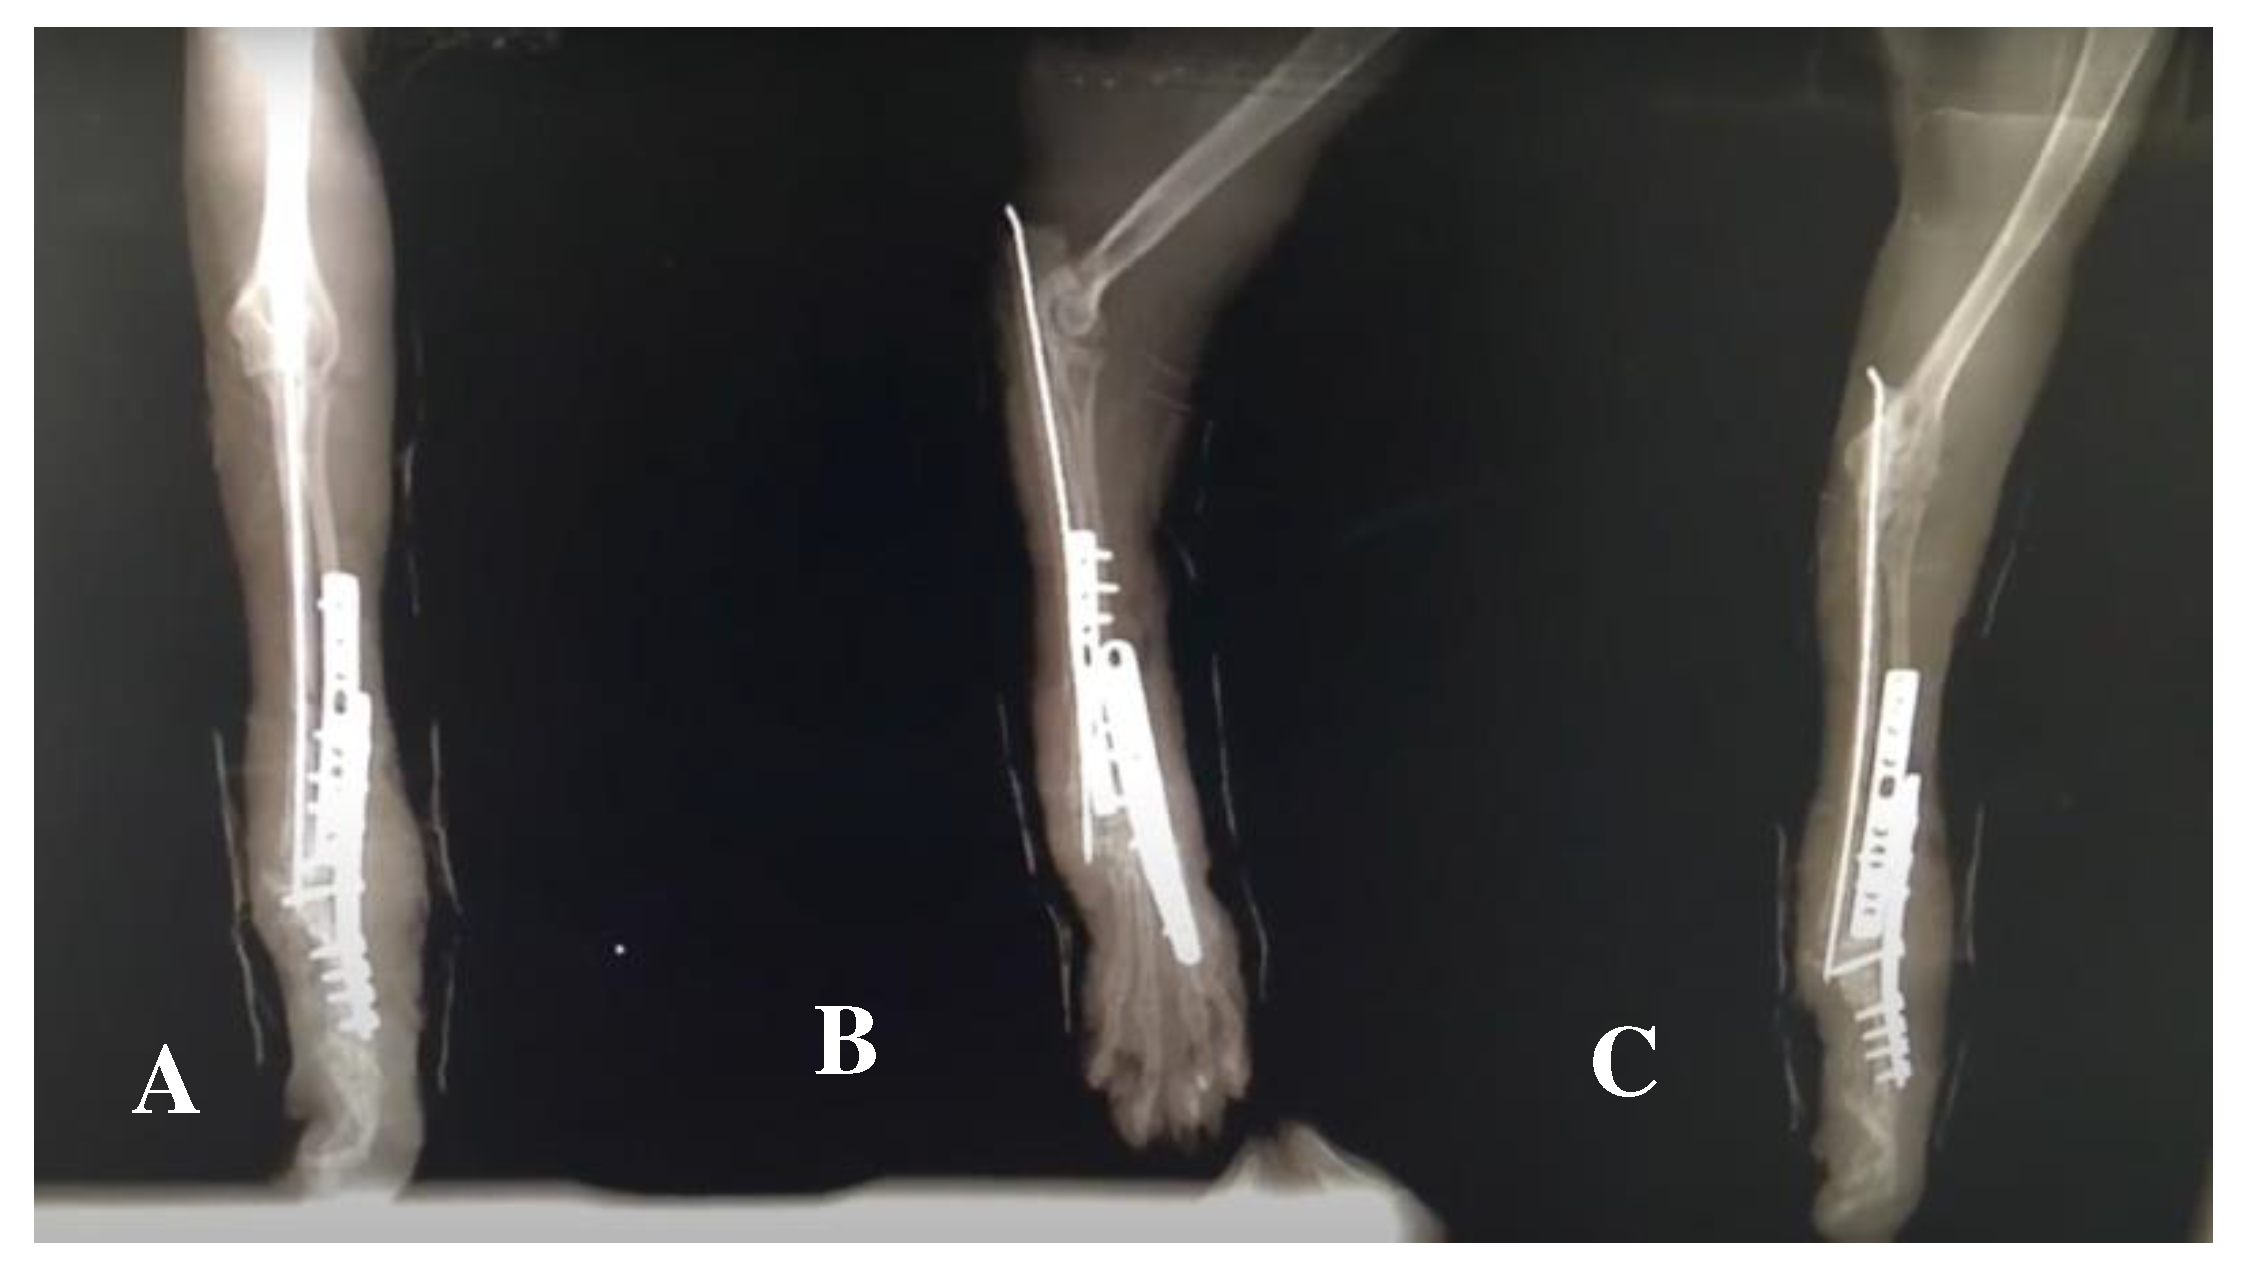

| Rehabilitation modality/exercise | Parameters | Implementation |

|---|---|---|

| Laser Therapy (A) |

18-22 J Class IV Laser Radial nerve pathway; SID |

Regenerative Role |

| 5-10 J Class IV Laser 4-point joint technique; SID (Shoulder, Elbow, Carpus) |

Analgesia, Anti-inflammatory effects | |

| FES of the radial nerve (B) |

30 – 40 Hz; 6-16 mA Trapezoidal modulation 1:4 duty cycle 2-4 s ramp up; 8 s plateau; 1-2 s ramp down; 10 min; TID |

In Deep pain positive |

| 30 – 40 Hz; 6-24 mA Trapezoidal modulation 1:4 or 1:5 duty cycle 2-4 s ramp up; 8 s plateau; 1-2 s ramp down; 10 min; TID |

In Deep pain negative | |

| Range of motion exercises (C) |

10-30 sets 4-6 times/day; |

All joints: shoulder, elbow, carpal and digits |

| Postural standing position (D) |

2-3 min 4-6 times/day |

|

| Ultrasound (E) |

1 MHz; 1.5 w/cm2; 10 min Pulsed mode; Duty cycle of 20%; Pulse ratio 1:4; 5 cm transduced head; |

Muscles: Triceps brachialis; Biceps brachialis; Extensor carpi radialis; Lateral and Common digital extensor |

| FES: Functional electrical stimulation; J: Joule; Hz: Hertz; mA: Miliampere; s: seconds; MHz: Megahertz. | ||